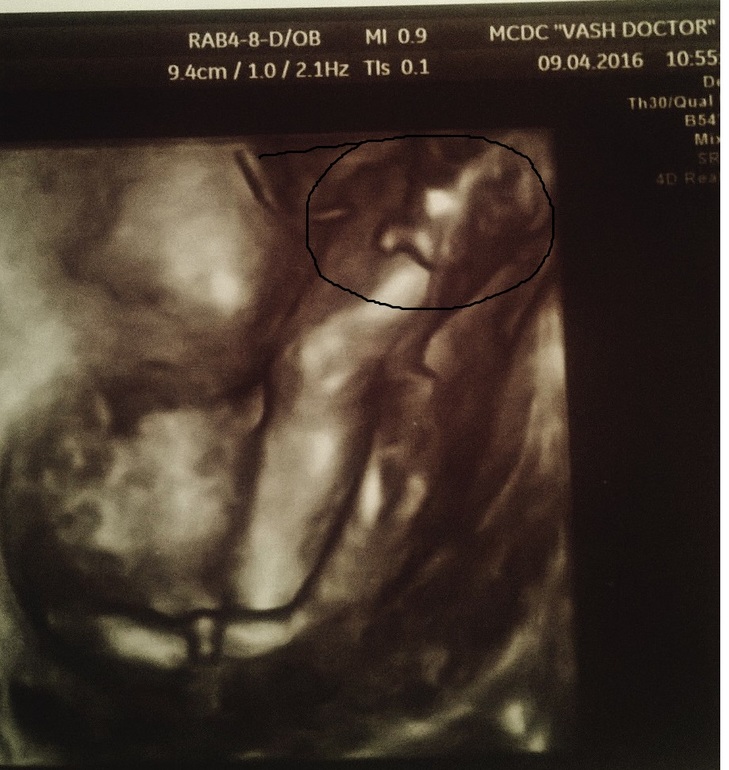

В субботу( 9 апреля ) у нас был 2 скрининг .

Ходили втроем, посмотрели масика, правда личико не показал, т.к. плацента по передней стенке и он прям личиком к ней... и на 4д плацента как туман и не видно личико

Зато все другие части видно прекрасно! Прям попка такая сладенькая) Ножки , ручки -ми-ми , все такое клевое))))

Вот наше фото 4 д , лицо не рассмотрели и врач предложила сделать фото того, что видно отчетливо

Наш перчик)